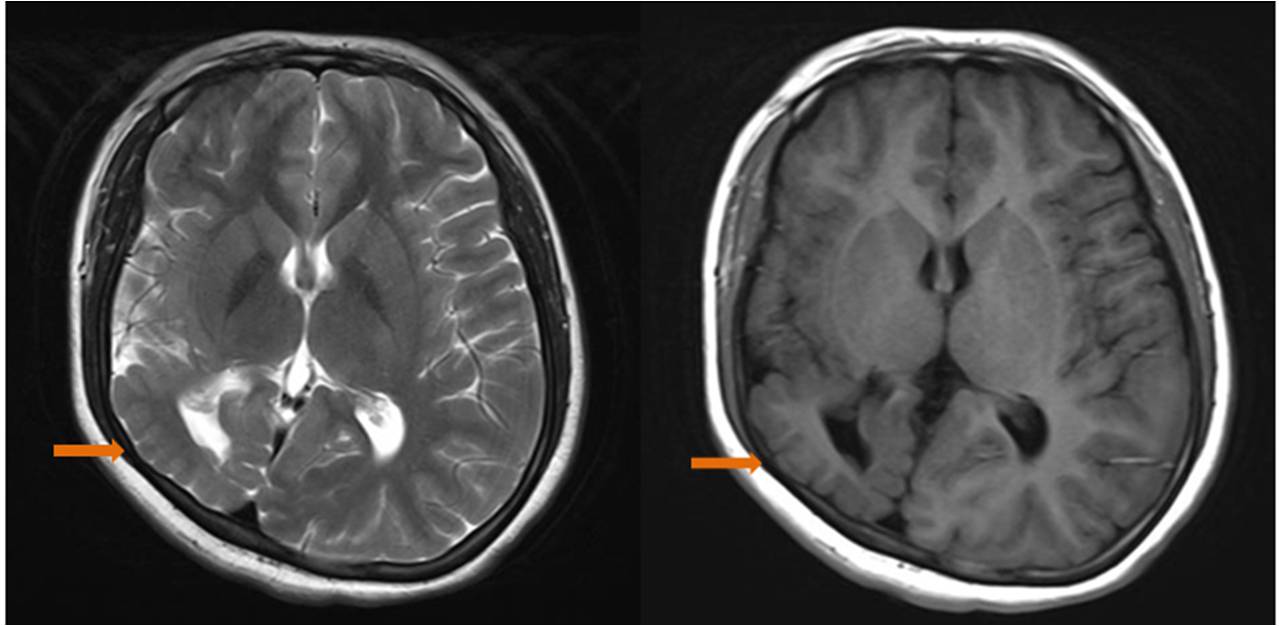

女,25歲,右側(cè)枕葉多微腦回畸形,白質(zhì)減少,右側(cè)側(cè)腦室后角不規(guī)則形擴大;頭顱不對稱,右側(cè)發(fā)育小。